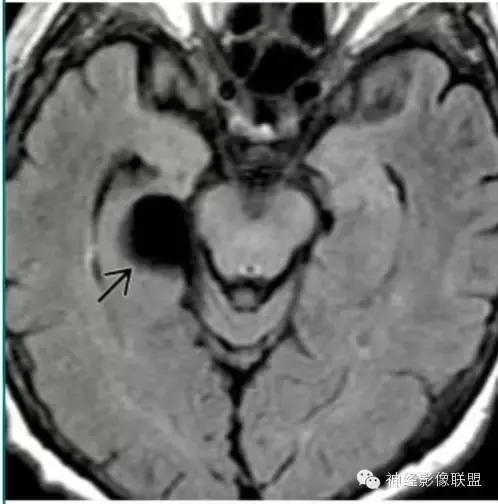

脑包虫囊肿